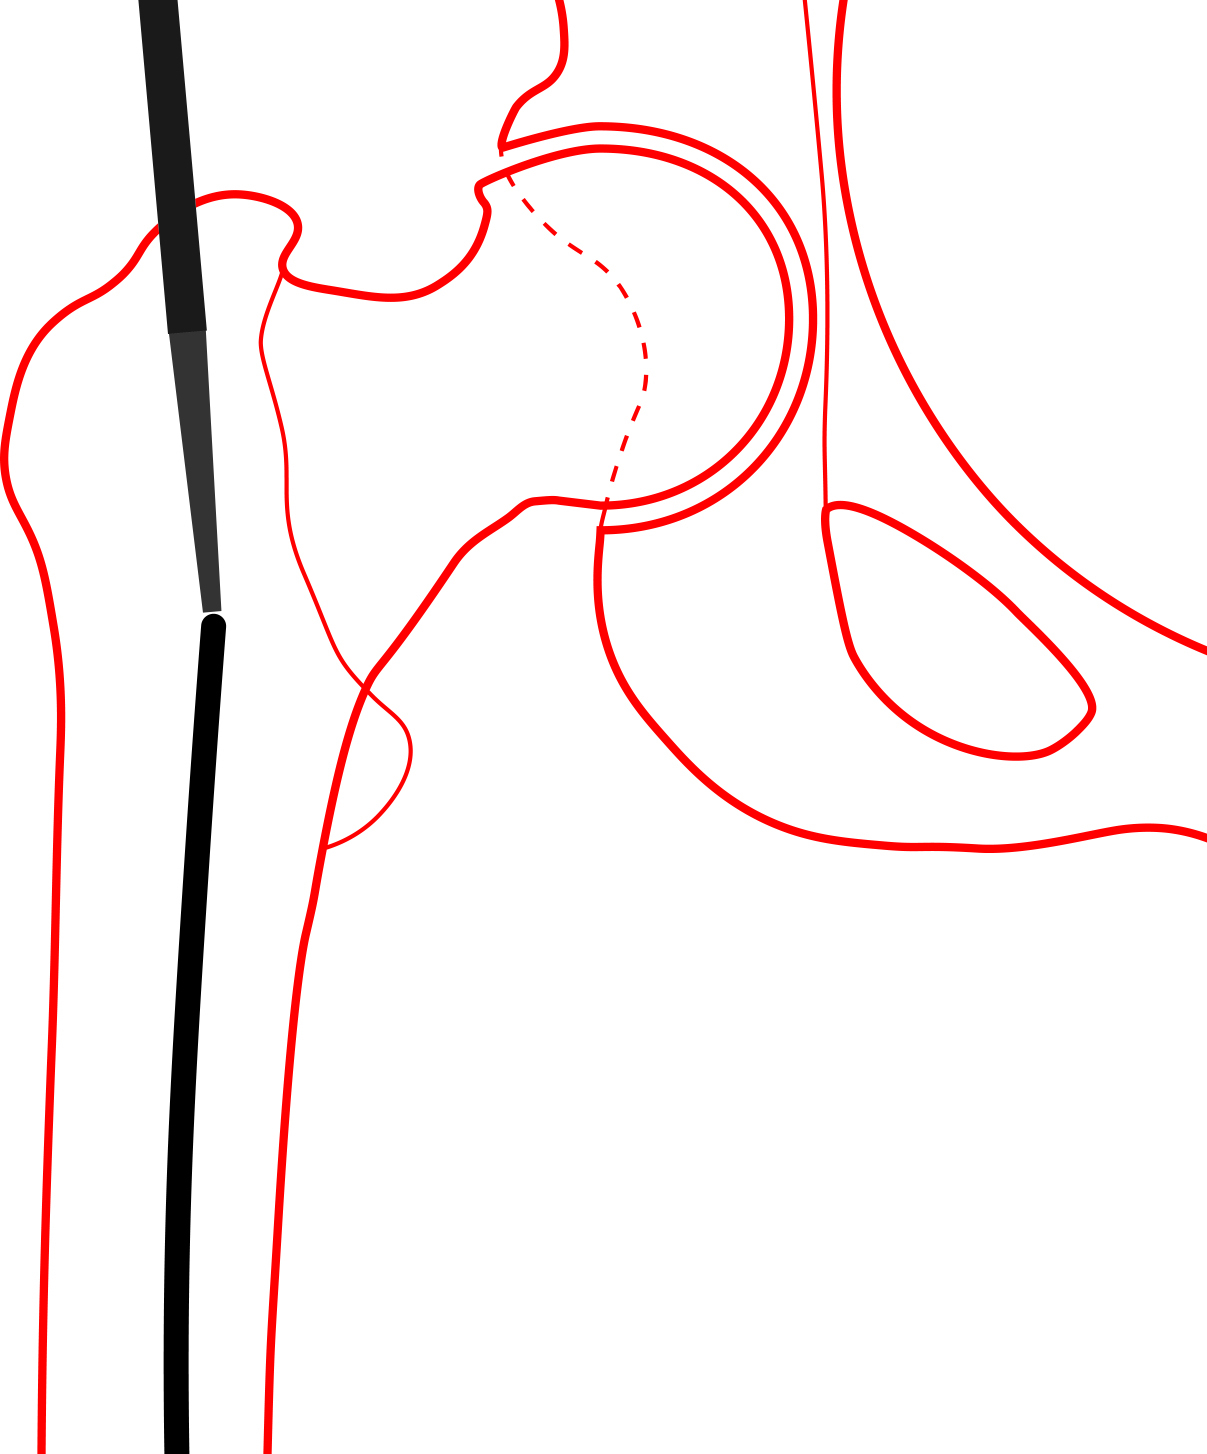

Multiple failed attempts were made to remove the guidewire using Kocher forceps, arthroscopic basket forceps, needle drivers, and Kerrison rongeurs (see Figure 1). Additional fluoroscopic images of the distal femur were subsequently obtained, revealing the guidewire to be inadvertently impacted into the subchondral bone of the distal femoral condyle (see Figure 2). Due to the inability to retrieve the guidewire using other extraction methods, a decision was made by the surgeons to remove the guidewire antegrade through the distal femoral condyle.

Traction on the operative leg was first released. The knee was then flexed to approximately 30° and held in the flexed position by a surgical assistant. A bone tamp was placed into the opening of the proximal femur and placed in direct contact with the guidewire (see Figure 3). A mallet was then used to gently tap the guidewire through the anterior aspect of the medial femoral condyle. The guidewire was advanced until tenting of the skin over the anterior knee was noted. A stab incision was made over the tip of the guidewire, and it was gently advanced further. Once enough guidewire was exposed, it was subsequently removed with a power drill.